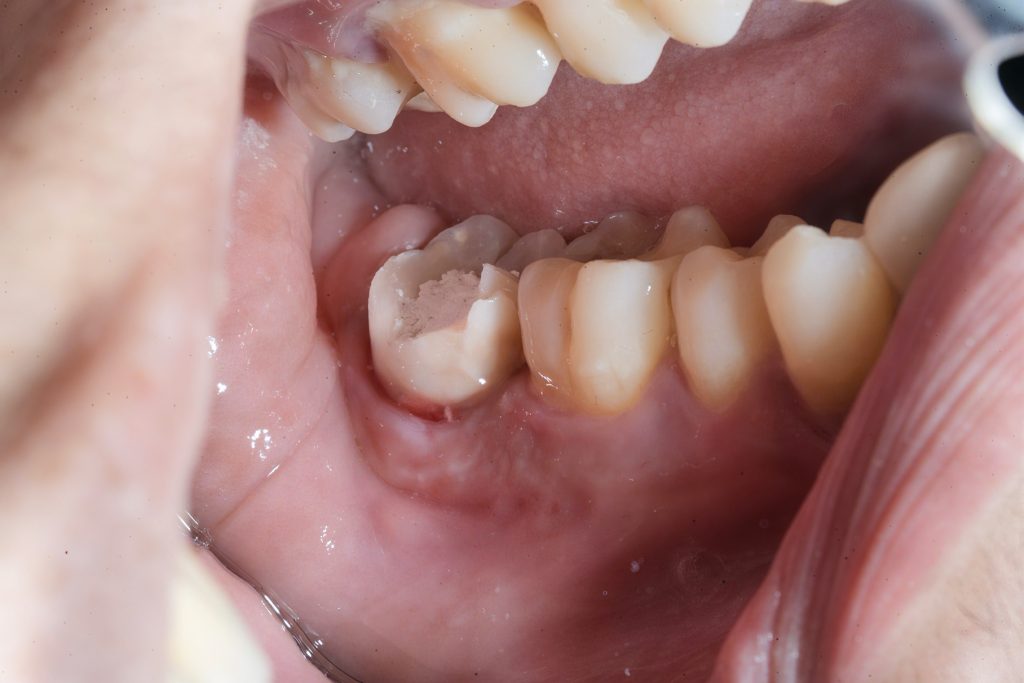

Clinical and radiographic evaluation showed a large Class V lesion extending below the CEJ with pulpal involvement and secondary dentin sclerosis (Fig 1 & 2).

1️⃣ Pre-operative view showing deep Class V caries